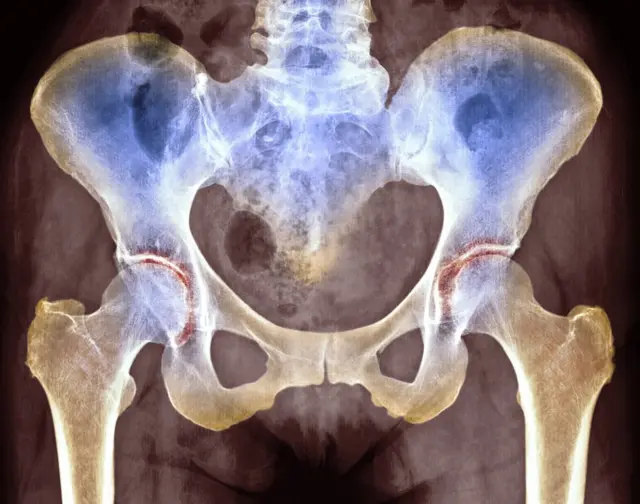

ที่มาของภาพ, Getty Images

ทีมวิจัยจากคณะแพทยศาสตร์ มหาวิทยาลัยดุ๊ก (Duke University) ของสหรัฐฯ รายงานการค้นพบดังกล่าวในวารสาร Science Advances โดยชี้ว่ากระดูกอ่อนในข้อต่อของมนุษย์ เช่นที่ข้อสะโพก ข้อเข่า และข้อเท้า สามารถซ่อมแซมตนเองได้ ซึ่งตรงข้ามกับความเข้าใจทางการแพทย์ที่มีมาแต่เดิม และน่าจะเป็นความสามารถแฝงที่ได้รับตกทอดมาจากบรรพบุรุษที่เป็นสัตว์เลื้อยคลาน

ผลปรากฏว่าข้อต่อในส่วนต่าง ๆ ของร่างกายมนุษย์ มีสัดส่วนของโปรตีนจำพวก "คอลลาเจนอายุน้อย" ที่ผลิตขึ้นใหม่ไม่เท่ากัน โดยข้อเท้าจะมีปริมาณของคอลลาเจนใหม่ดังกล่าวอยู่มากที่สุด ในขณะที่ข้อเข่ามีคอลลาเจนอายุปานกลางอยู่เป็นสัดส่วนมากกว่า ส่วนข้อสะโพกนั้นมีคอลลาเจนเก่าซึ่งมีอายุมากในปริมาณสูงสุด

ที่มาของภาพ, SCIENCE PHOTO LIBRARY

ผลการศึกษานี้อาจเป็นคำตอบได้ว่า เหตุใดโรคข้อเสื่อมและอาการบาดเจ็บที่ข้อสะโพกและข้อเข่า จึงรักษาให้หายได้ยากและช้ากว่าที่ข้อเท้า